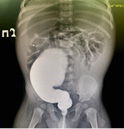

Выполнено инструментальное обследование: ретроградное рентгеноконтрастное исследование нижних отделов толстой кишки (ирригография) (рис. 1), магнитно-резонансная томография (МРТ) крестцово-копчиковой области (рис. 2), в ходе которого на основании клинической картины (хронического толстокишечного стаза), наличия аномалий строения анального канала (стеноз), а также выявленных аномалий дистальных отделов позвоночника установлен диагноз: врожденный стеноз анального канала в составе синдрома Куррарино, осложненное хроническим толстокишечным стазом, мегаректум.

Рисунок 1.

Расширенные нижние отделы толстой кишки, праворасположенная сигма. Опорожнение не получено. Рельеф складок слизистой толстой кишки не изменен. Область анального канала сужена (ирригография)

Figure 1.

Enlarged lower colon, right-angled sigma. Emptying was not received. The relief of the folds of the colon mucosa is not changed. The anal canal area is narrowed (irrigography)